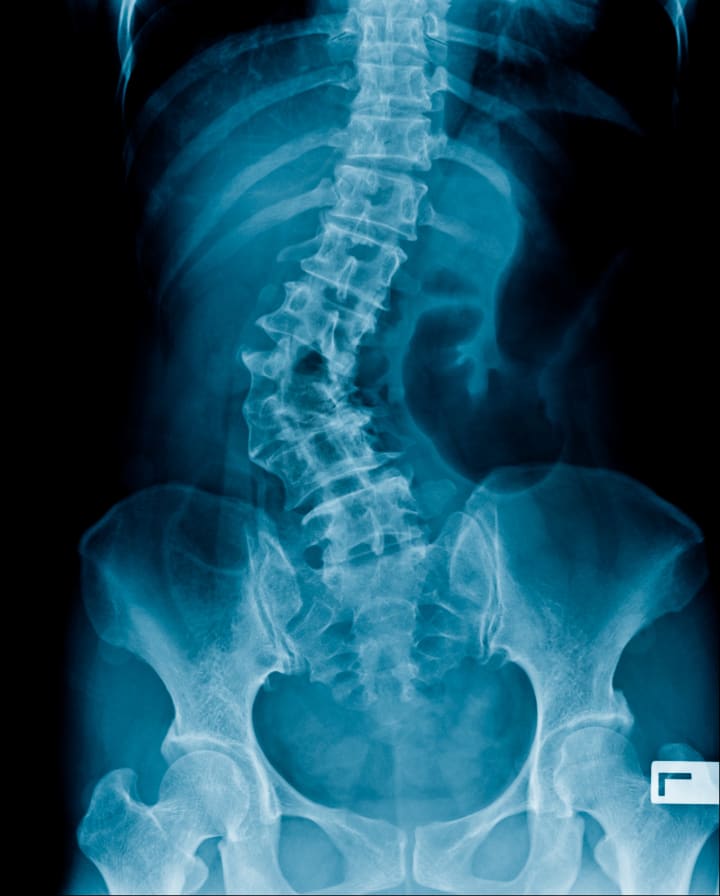

Scoliosis, or an abnormal curvature of the spine, can be more common in people with EDS due to the connective tissue's role in supporting the spine. Treatment options can include bracing, physical therapy, and in severe cases, surgery.